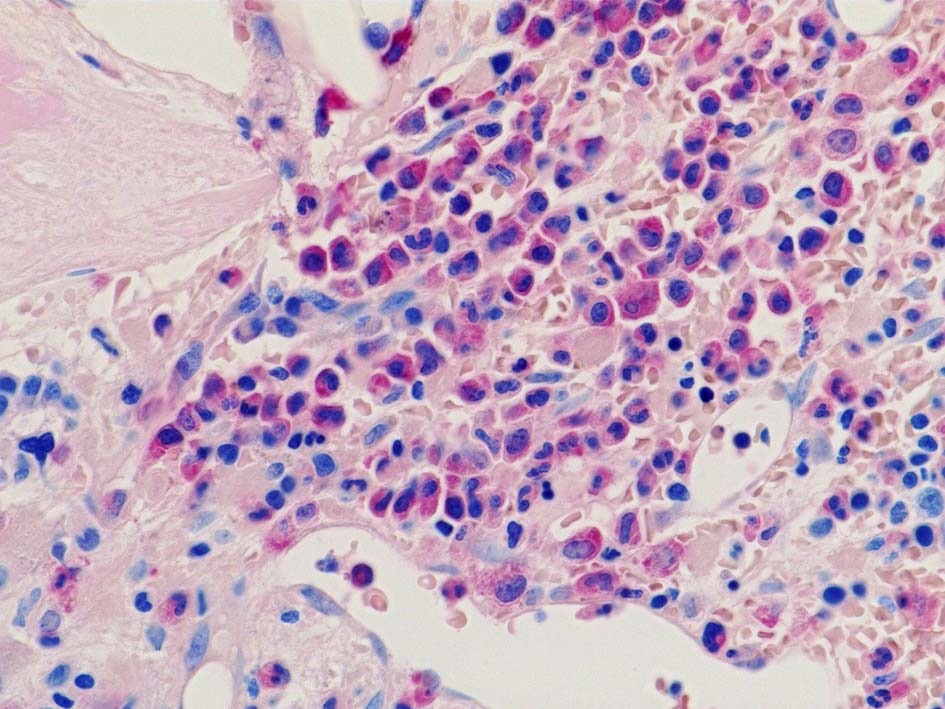

Case02; Meylofibrosis, overt fibrosis

77year-old female. 40歳時polycythemia veraと診断されていた.

黒染する弾性線維の増生のほか, 赤く染まる膠原線維の増生が確認される. MF-2 fibrosis. 鍍銀染色の核染色をすると膠原線維の赤染がわからなくなるので行わない.